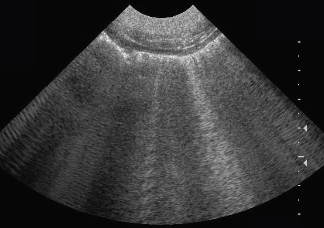

Lequel est anéchogène?

la vessie (remplie de liquide)